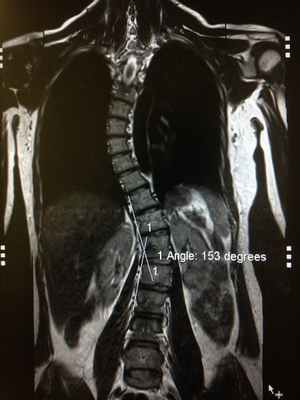

На мр-изображении видно, что большая поясничная мышца находится в состоянии отека, о чем свидетельствует изменение сигнальных характеристик. (гиперинтенсивная, яркая по t2)